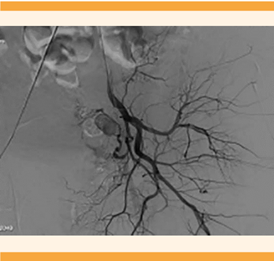

A su llegada al hospital de tercer nivel, la paciente se encontró estable y con sangrado en menor cantidad, pero persistente. Fue valorada por el radiólogo. Ante la sospecha de una malformación vascular se decidió proceder a la arteriografía pélvica en la que se objetivó una formación sacular, dependiente de la arteria hipogástrica izquierda, compatible con un pseudoaneurisma (Figuras 3 y 4) que justificaba la clínica de la paciente. Por ello, se decidió practicarle un cateterismo con embolización selectiva de la rama aferente del pseudoaneurisma, que concluyó sin contratiempos y se comprobó la ausencia de flujo a la formación aneurismática posterior a la embolización. Figura 5